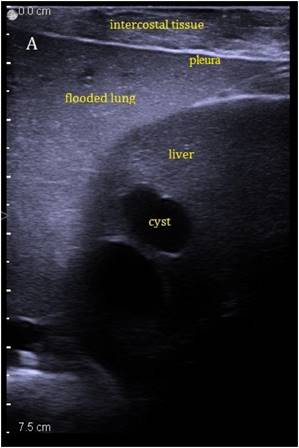

The liver could be examined sonographically trough the flooded lung in all animals. Thereby the lung appeared brighter in echogenity than the liver. In between liver and lung, the diaphragm was visible as an echogenic demarcation (Figure 3A). The flooded lung showed no signs of residual gas content in all animals. Immediately after HIFU insonation a hyperechoic region appeared in B-mode images at the focal position (Figure 3B). Their intensity decreased continuously but remained visible.

Figure 3

Sonographic imaging of the liver through the flooded lung before and after HIFU insonation. A) Transthoracic image shows subcutaneous tissue, pleura, flooded lung and liver. B) Immediately after HIFU insonation a well-demarcated hyperechoic sonolesion occurs in the liver. The yellow dashed line indicates the HIFU beam.